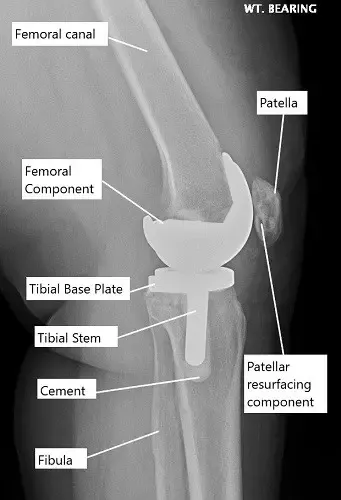

X-ray showing a total knee replacement.

Total knee replacement removes the worn surfaces in all three compartments. The bone ends are shaped so metal parts fit securely, with a plastic insert in between. This is recommended when arthritis affects more than one compartment or when the knee has deformity, ligament damage, or meniscus problems.